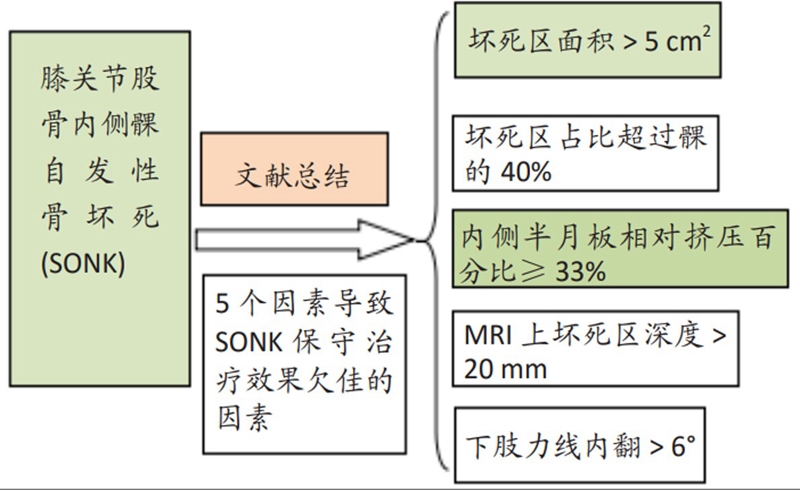

关于影像学评估与SONK的预后的关系,多项研究表明小于3.5cm2的小坏死病变可进行保守治疗,在冠状位X片上5cm2软骨下病变面积作为预测预后不良和高风险进展的临界值,前后位X片坏死区>50%髁,会迅速塌陷,病变范围很大(>40%髁/前后位X 片)或有早期骨关节炎的影像表现,保守欠佳。

早期(3月内)内侧半月板相对挤压百分比≥33%,是SONK发病1年后预后不良的预测指标,MRI检查没有局灶性轮廓塌陷和髁深处没有低信号线(隔离带),预后好,股胫角>180°(下肢力线内翻>6°)和MRI上深度>20mm 预示SONK患者症状发作后1年预后不良。

影响保守治疗效果的因素

如果保守治疗3个月后症状没有减轻或MR上没有改善时,患者同时存在5个因素中的任一个,则应考虑行手术治疗,选择膝关节镜+自体骨软骨移植术(当患者下肢力线内翻<3°时)、膝关节镜+HTO术、或膝关节镜+HTO+坏死区病灶刮除+自体植骨术。

需在考虑5个因素的基础上,同时兼顾考虑年龄、性别和活跃程度,分别选择用膝关节镜+自体骨软骨移植术(当患者下肢力线内翻<3°时)膝关节镜+HTO术+微骨折术、膝关节镜+HTO+坏死区病灶刮除+自体植骨术或单髁置换术。

由于存在继发退行性改变,一般不建议单纯行膝关节镜+自体骨软骨移植术。需在考虑5个因素的基础上兼顾患者年龄、性别和活跃程度,分别选择膝关节镜+HTO术+微骨折术、膝关节镜+HTO+坏死区病灶刮除+自体植骨术或单髁置换术。对于合并症状性髌股关节炎、外翻畸形、坏死区范围大影响单髁假体稳定性等的Koshino Ⅳ期膝关节股骨内侧髁SONK,采用全膝关节置换术。